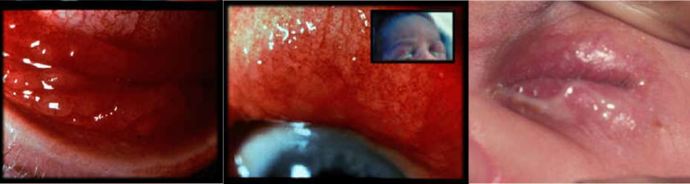

Chlamydial eye infection often presents unilaterally and becomes a bilateral conjunctivitis. This may initially be serosanguineous but later becomes mucoid or mucopurulent in appearance. It is commonly associated with eyelid swelling and marked conjunctival injection (Figure 2). Onset is usually around day 5-14 but may be as late as 60 days. 10-20% of infected neonates develop pneumonia and infants may have feeding difficulties at initial presentation as a consequence of this.

Figure Two: Infants with chlamydial eye infection